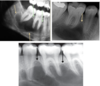

What is this radiographic finding?

Periapical Cyst

What are these radiographic findings?

Residual Cysts

What is the radiographic finding?

Residual Cyst